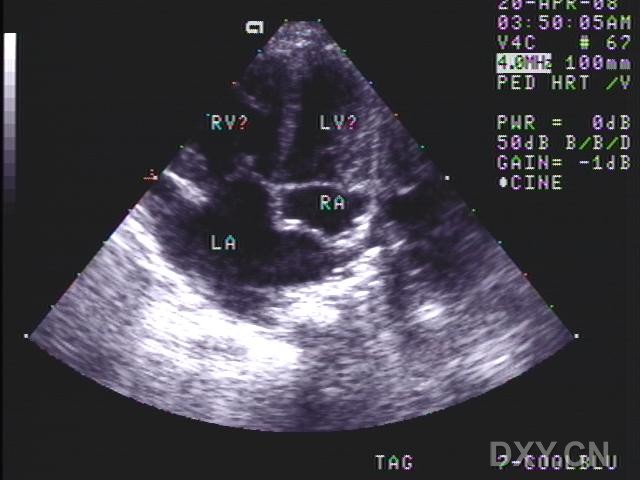

心间隔缺损

图片尺寸640x480